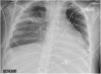

Un varón de 38 años sin antecedentes médicos relevantes, fue hospitalizado en la unidad de cuidados intensivos con fiebre y síntomas respiratorios inespecíficos, que progresaron rápidamente a insuficiencia respiratoria grave, shock séptico y fracaso multiorgánico. Requirió soporte vasopresor, ventilación invasiva y tratamiento antibiótico con penicilina, clindamicina y linezolid al aislar Streptococcus pyogenes en muestras respiratorias y hemocultivos. A pesar del tratamiento, persistieron la fiebre, al igual que una consolidación en la radiografía de tórax (fig. 1, flecha). La tomografía computarizada reveló necrosis (fig. 2, estrella) y absceso (fig. 2, flecha) pulmonar en el lóbulo superior derecho. Este caso destaca una presentación grave de infección invasiva por S. pyogenes, resaltando la necesidad de considerar esta etiología en el diagnóstico diferencial, incluso en pacientes sin factores de riesgo conocidos.